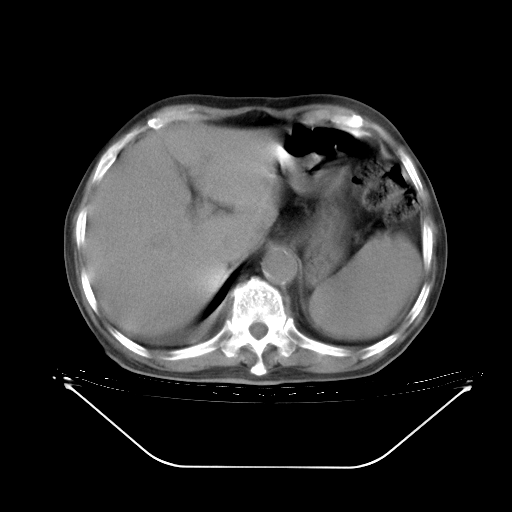

胸腹部CT,诊断意见:左上肺叶钙化灶、左侧胸膜局限性增厚并钙化、胆囊炎。描述部分肺组织呈磨玻璃样改变。